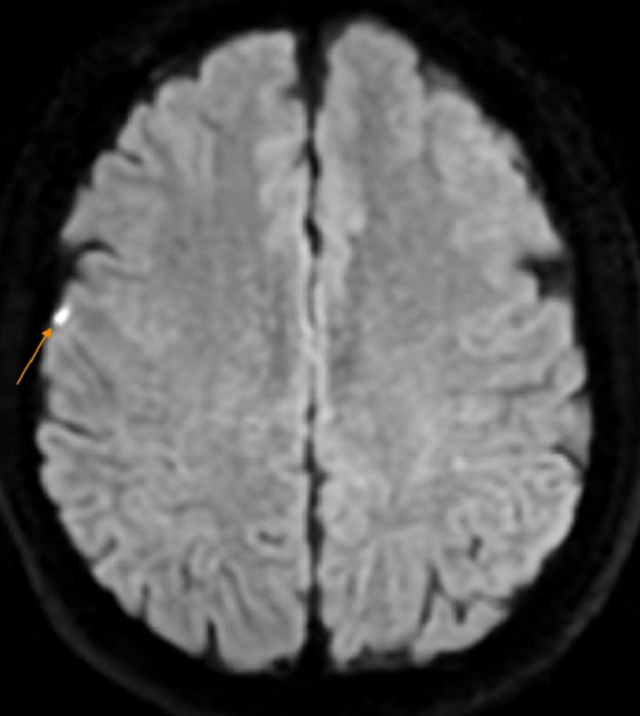

Để đi đến chẩn đoán xác định, bệnh nhân được chỉ định làm các xét nghiệm cận lâm sàng chuyên sâu, đáng lưu ý kết quả chụp MRI sọ não có hình ảnh tổn thương nhỏ vỏ não vùng đỉnh phải (theo dõi nhồi máu não): Thoái hóa myelin chất trắng dưới vỏ bán cầu đại não và quanh não thất bên hai bên (phân loại Fazekas độ 1); Thiểu sản động mạch não trước bên trái đoạn A1; Viêm xoang sàng hai bên.

BS Hoàng Anh Tuấn chia sẻ: Sau khi khám và làm các cận lâm sàng cần thiết có chẩn đoán xác định bệnh nhân bị nhồi máu não bán cấp/viêm gan B. Tuy nhiên, đây cũng là trường hợp may mắn phát hiện và điều trị kịp thời để tránh gây hậu quả nghiêm trọng như gây ảnh hưởng tới khả năng vận động, ngôn ngữ, nhận thức và thị giác của người bệnh.